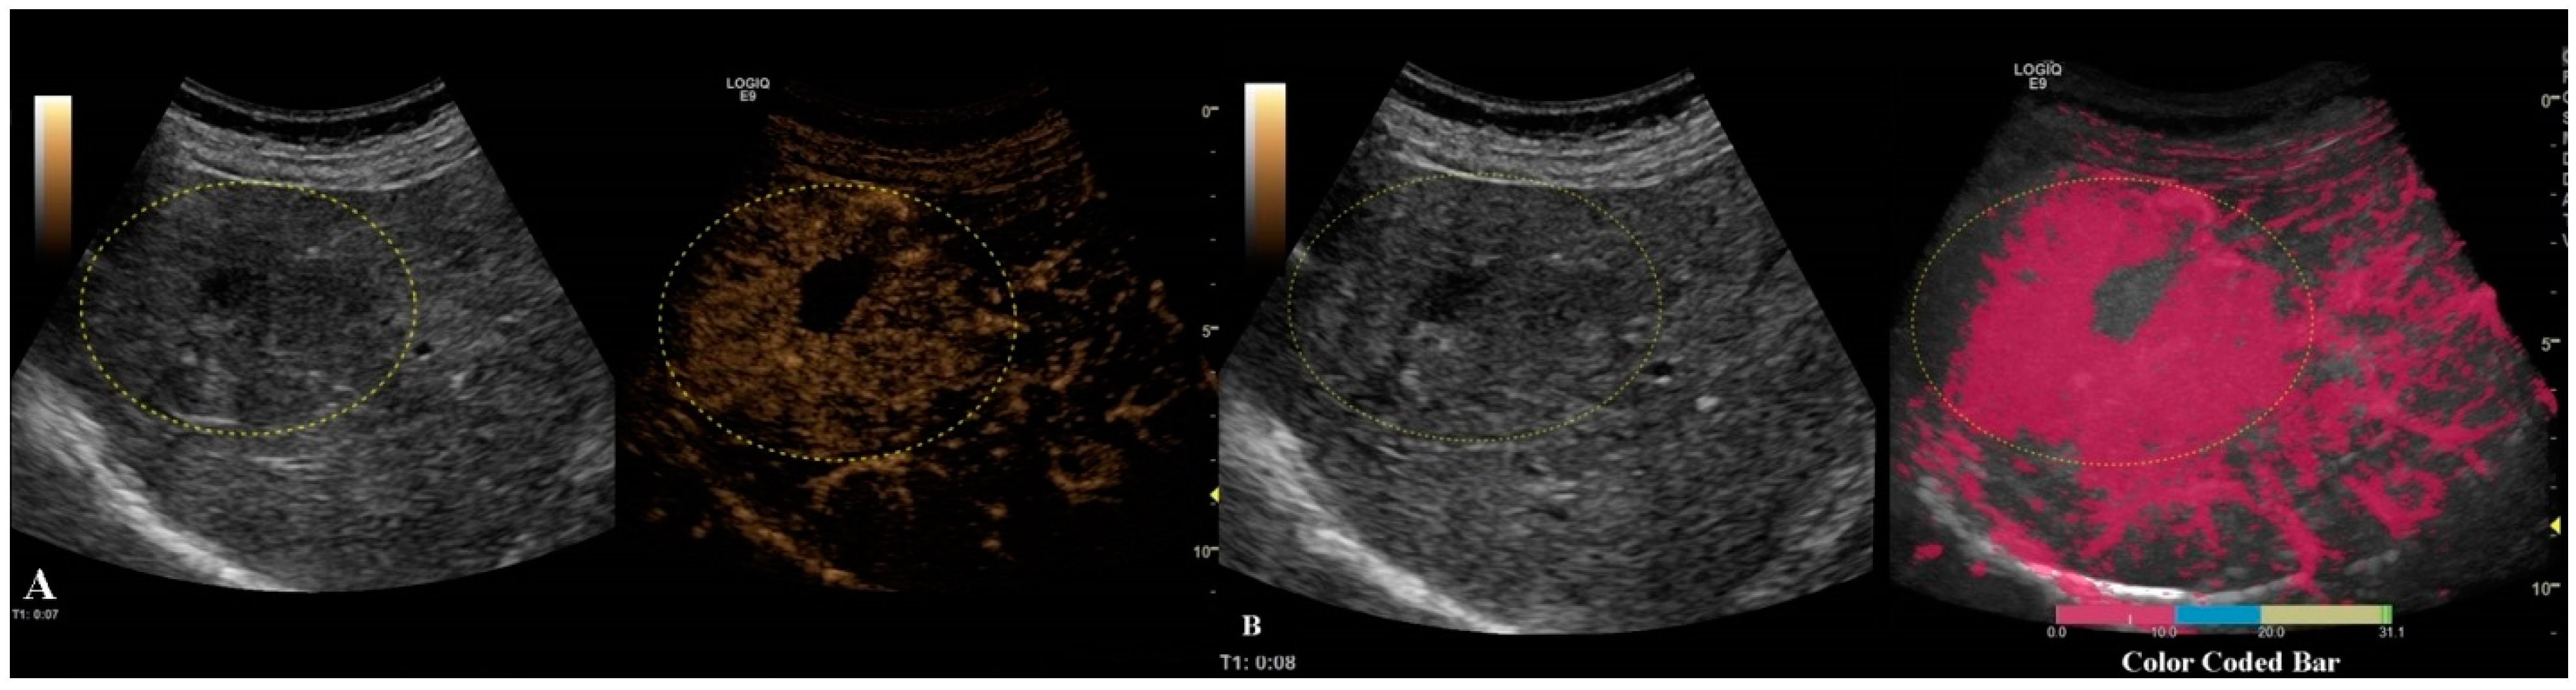

The second step was to quantitatively analyze the tissue perfusion in the late phase of CEUS evaluation using the TIC feature, and to highlight the presence of FLL washout. CEUS examination was performed with the C1-6 convex probe following the CEUS guidelines for the liver. The contrast agent used was SonoVue® (Bracco SpA, Milan, Italy), given as an intravenous bolus of 1.7 mL of SonoVue, followed by 10 mL of saline [1,2]. The late phase (>120 s) of each lesion was reassessed and evaluated via time–intensity curve analysis. The curve fitting parameters for the washout in the bolus injection were time to peak, area under the curve, maximum gradient, and curve gradient, which were evaluated in order to depict the slightest washout phenomena of the lesion. Curve fitting for washout was calculated with the following formula: Washout: F(t) = Aexp(−kt) + B (as explained in Figure 3) [10]. Two regions of interest were selected, one outlining the lesions and the second reference region near the parenchyma, which is possible to perceive at the same depth. All of the lesions’ washout phases were evaluated using TIC.

The only TIC-CEUS parameter that showed significant differences between malign and benign lesions was AREA (−25.08 ± 37.98 and −7.08 ± 42.6, p = 0.04). The parameter AREA is in fact the area under the curve. The curve fitting algorithm is applied and a curve is obtained according to the intensity observed. Some examples of fitted curves are shown in both Figure 4a,b, where parameter AREA is the area under the fitted curve. Since the washout is characterized by a smaller intensity of activity, the observed curve will fall and hence the fitted curve will fall, too. This fact leads to a smaller AREA parameter. This phenomenon allows us to impose a threshold on the AREA parameter in order to detect the washout. We also tested A (the difference between B and the intercept intensity at t = 0), B (the minimum intensity at t = infinity), k (the gradient at t = 0, calculated by “−A*k”), TtoPk (time to peak intensity from the start frame to the end frame), but without any statistical significance (all p-values > 0.05) (Table 3).

Figure 5. In this setting, a malignant lesion was assessed, as depicted in B-mode (A). CEUS evaluation is depicted in frames (BD). In frame (D), the enhancement pattern is not recognizable; thus, TIC analysis (E) was applied. The results revealed objective washout phenomena (the graphs are intersecting one another).